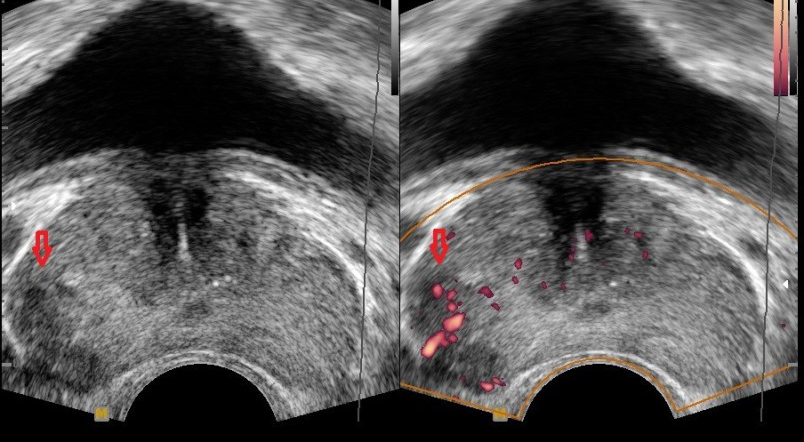

전립선암 초기증상 9. 혈뇨

혈뇨는 소변에 피가 섞여 나오는 증상으로, 상식적으로 신장이나 방광에 문제가 있다는 신호일 수 있으기 때문에 미리 체크를 받아보는 것이 좋아요. 전립선암도 혈뇨의 흔한 원인인데요. 전립선의 암세포는 전립선으로 출혈을 일으켜 혈뇨를 일으킬 수 있지만, 혈뇨는 전립선암의 흔한 증상일 뿐 아니라 요로감염이나 전립선의 거시적 문제와 같은 다른 일시적인 원인으로도 확인될 수 있어요.